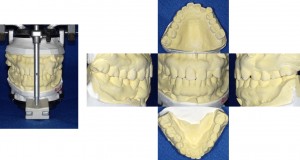

口腔内写真

口腔内写真も必要となります。図は5枚法といわれるもので、正面像、左右側面像、上顎咬合面像、 下顎咬合面の計5枚を撮影したものです。必要に応じて、9枚法の撮影を行うこともあります。

歯の模型

コンサルティング用に印象を採得し、歯の模型を作製します。お口の中を奥まで再現することで、歯列全体を確認することができます。また、矯正治療後の歯並びをシミュレーションするために、セットアップ模型も作製します。これにより、術前・術後でどのように改善されるかを確認しながら患者さんにより分かりやすくお伝えすることができます。

術 前

セットアップ模型